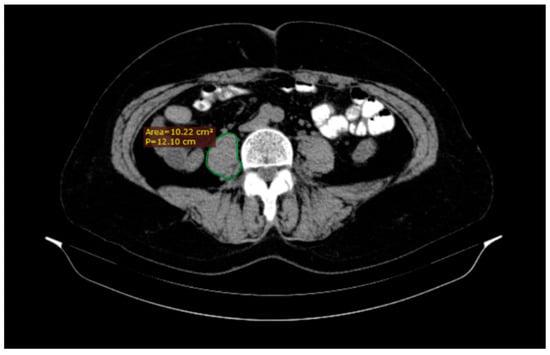

A radiologist analyzed all CT scans on a standard desktop computer screen using Radiant DICOM Viewer (Medixant, Poznan, Poland) and IQ View (Precision Diagnostic Systems, Inc., Landrose, USA) software. We used the CT images to assess the psoas muscle area and psoas density for each patient (Figure 1). The level of the L3 vertebra was selected as a landmark on the cross-sectional horizontal image and the psoas muscle area was traced (cm2) as the region of interest of the iliopsoas muscle contour. The total psoas area was calculated by the sum of the left and right psoas area, and then normalized by using each patient’s height to produce a PMI in cm2/m2. At the same time, the mean psoas muscle density (right psoas muscle density + left psoas muscle density/2) was measured in Hounsfield Unit (HU) [,].

Figure 1.

A quick tracing of the right (R) psoas muscle at the third lumbar vertebra (L3) level using DICOM Viewer software which automatically generates the area.